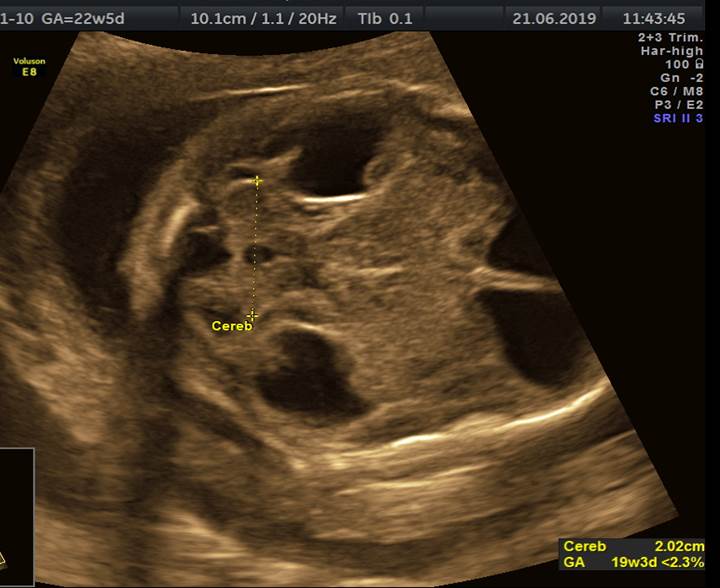

Вопрос 4

Срок 22 недели 5 дней. Вентрикуломегалия тяжелой степени. Пол плода — женский. В какой части головного мозга скрывается основной диагноз?

Трансцеребеллярный скан и 3Д режимы

Ответ на вопрос 4

- Поиск основного диагноза нужно вести в области задней черепной ямки (смотрим НАЗАД).

- Очевидно, что полушария мозжечка уменьшены в размерах (фокальная гипоплазия полушарий мозжечка), червь сформирован правильно (об этом подробно поговорим на второй лекции).

- При консультировании — обязательно предлагаем инвазивную диагностику с лабораторным исследованием молекулярного кариотипа (ХММА).